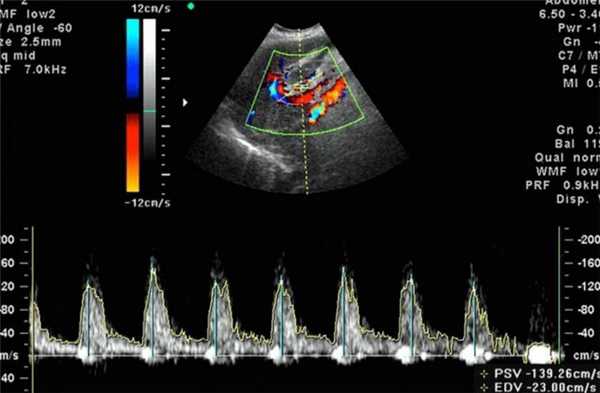

- Системное программное обеспечение должно быть в состоянии оценить пиковую систолическую скорость (ПСС), конечную диастолическую скорость (КДС) и индексы: например, пульсационный индекс (ПИ) и индекс резистентности (ИР) и систоло / диастолическое соотношение (С / Д).

Существует значительная разница в показателях допплера, измеренных на эмбриональной части пуповины, свободной части и плацентарной части пуповины. Для простоты и последовательности, измерения следует проводить в свободной части пуповины (Рис.3).

Методика проведения цветной допплерографии в средней мозговой артерии

- Исследование средней мозговой артерии проводится в аксиальном срезе головного мозга, на уровне таламуса и крыльев клиновидной кости. Полученное изображение необходимо увеличить.

- С помощью цветного допплера определяем Виллизиев круг и проксимальный отдел средней мозговой артерии (рис.5)

- Контрольный объем должен быть размещен в проксимальной трети CМA, около места отхождения со внутренней сонной артерией, поскольку систолическая скорость уменьшается с расстоянием от места отхождения данной артерии.

- Угол между ультразвуковой волной и направлением потока крови следует держать как можно ближе к 0 ° (рис. 6).

- По меньшей мере три записи должны быть получены и 10 последовательных кривых. Самая высокая точка волны оценивается, как пиковая систолическая скорость (PSV, см / сек).